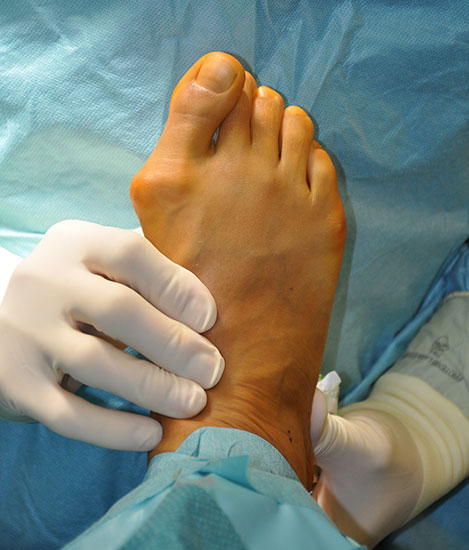

Abschließend erfolgt die klinische Kontrolle hinsichtlich Stellung, Alignement und passiver Funktion. Überprüfen der Sehnenspannung durch den retrocapitalen Push-up Test.